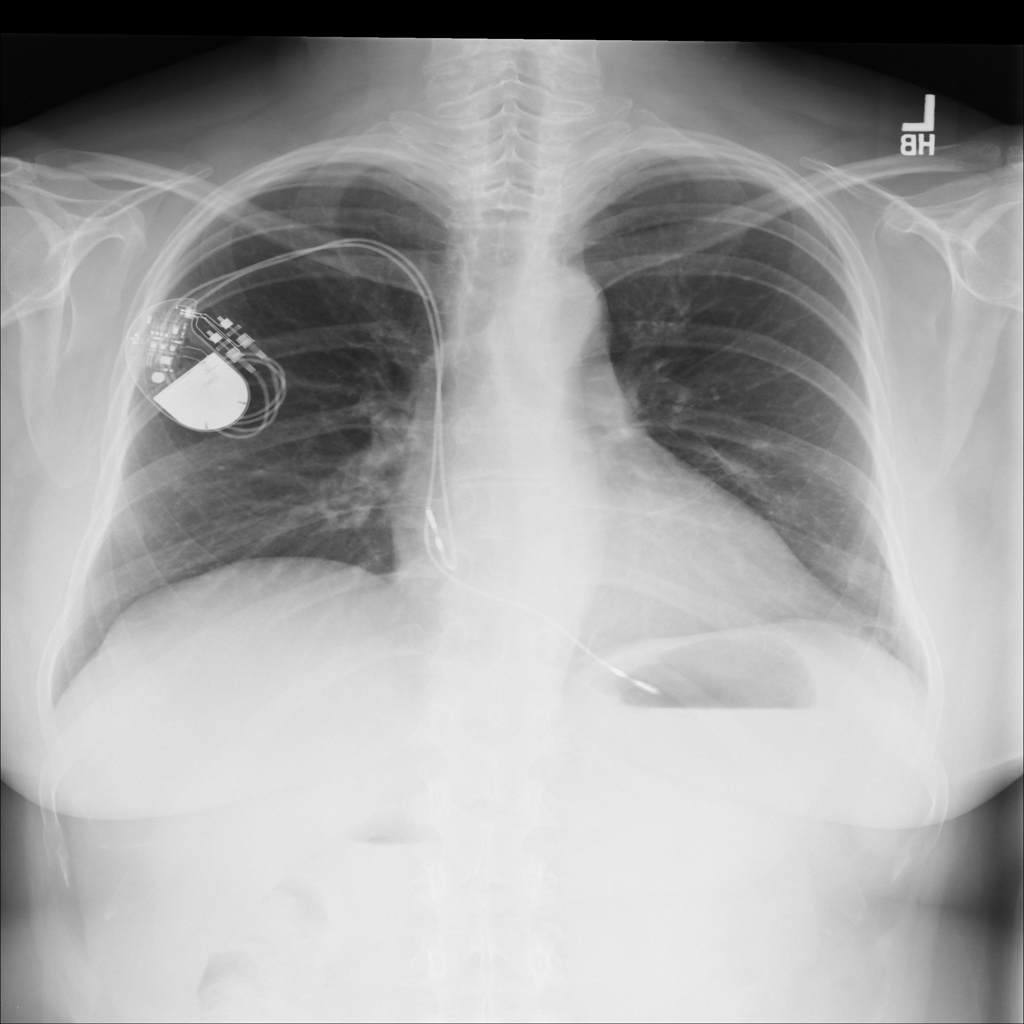

PAT-DB80 · IMG-000Atelectasis

PAT-DB80 · IMG-000

PA